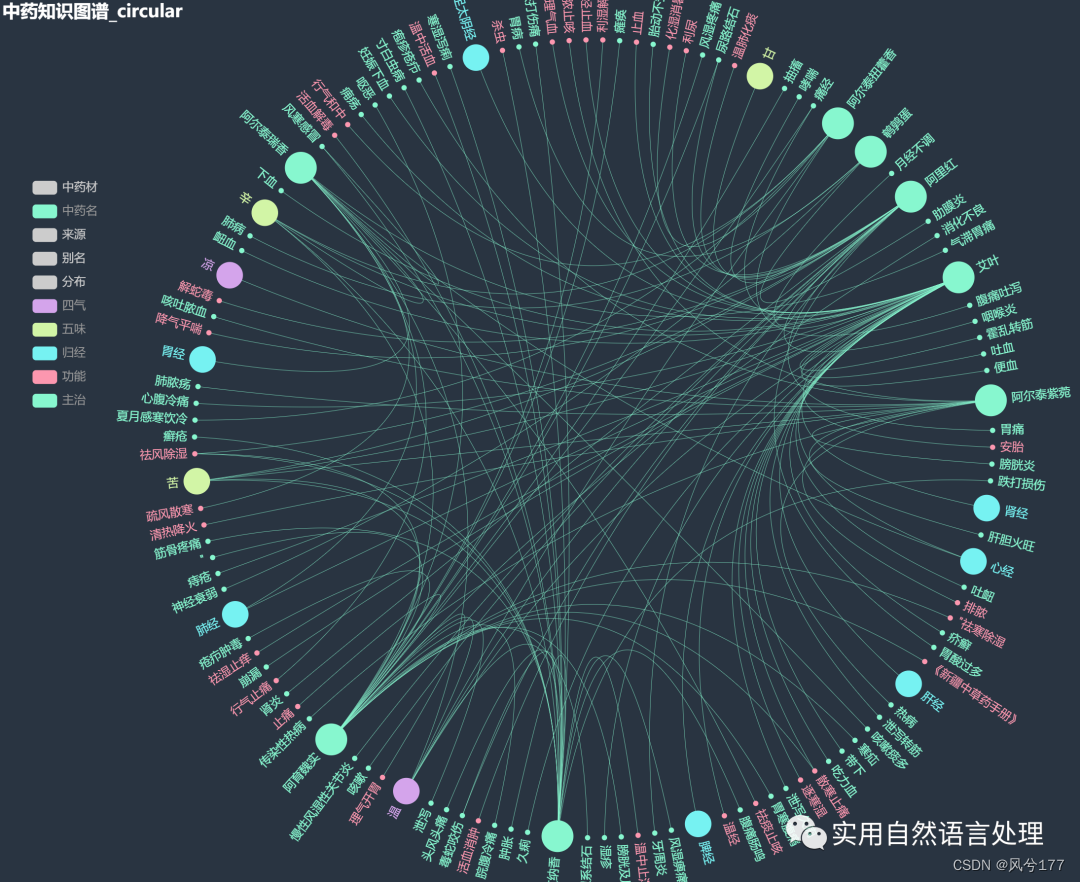

少量数据的中药知识图谱-环形图(部分节点展示图2)

本文将基于pyecharts框架,对中药材知识图谱进行“力导图”和“环形分布”可视化,同时,对中药材地理分布、来源和别名关系进行分析与可视化。

2.2 中药材知识图谱可视化

前文自顶向下构建中药知识图谱初探已经介绍了中药材知识图谱的构建和neo4j可视化过程,接下来将对该图谱数据利用pyecharts进行可视化。